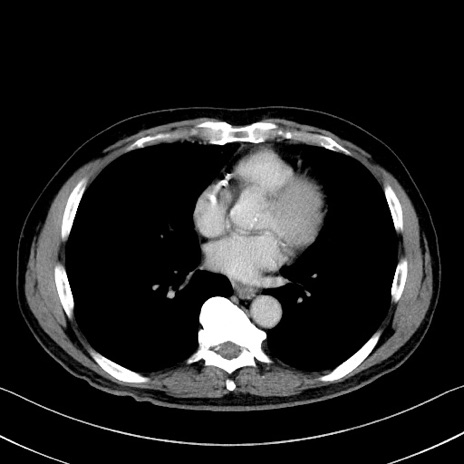

冠状断像